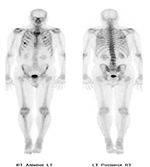

63 year-old woman with right femoral hardware for 3 years presented with right leg pain. Whole body Tc-99m HMPAO tagged WBC (A) scan demonstrated focal abnormal activity in the distal right femur which may represent infection or focal marrow. Tc99m sulphur colloid bone marrow scan (B) four weeks later demonstrates similar focal uptake in the distal right femur confirming the etiology as uptake in displaced marrow and not infection. 60 year-old man with history of lung cancer and left hip arthroplasty suffered from stiffness in the left hip region. Axial CT, FDG PET, fused axial, and coronal PET-CT demonstrates increased uptake of FDG in heterotopic ossification in the musculature of the left thigh. 30 year-old woman with history of lymphoma. Axial CT, PET, PET-CT fused, and PET MIP images demonstrate intense FDG activity in the bilateral neck and paravertebral regions with a symmetrical distribution. Cross-sectional images clearly show that activity in the neck corresponds to fat and therefore consistent with brown fat activity. Brown fat activity is seen more commonly in younger patients and is also increased in response to hypothermia (so keep patients warm both pre and post injection of FDG).

Figure 35A Figure 35B

PA Chest radiograph (A) demonstrates a sternal cage. Whole body Tc99m MDP images (B) demonstrate focal radiotracer activity in ribs bilaterally on the anterior view representing the sites of sternal cage fixation with bony reaction.